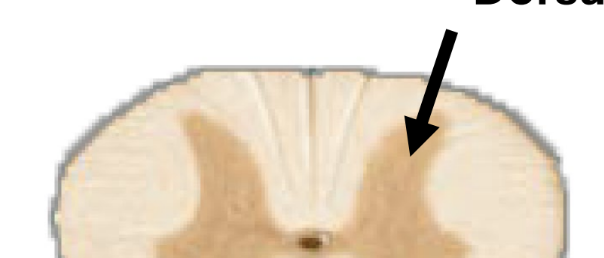

white matter

• contains bundles myelinated axons

• lipids in myelin sheath → white color

<ul><li><p>contains bundles myelinated axons</p></li><li><p>lipids in myelin sheath → white color</p></li></ul><p></p>

gray matter

• contains unmyelinated cell bodies of neurons

• forms “butterfly” shaped regions

• no myelin → gray color

<ul><li><p>contains unmyelinated cell bodies of neurons</p></li><li><p>forms&nbsp;“butterfly” shaped regions</p></li><li><p>no myelin → gray color</p></li></ul><p></p>

ventral gray horn

cell bodies for motor neurons

<p>cell bodies for motor neurons</p>

dorsal gray horn

cell bodies for sensory neurons

<p>cell bodies for sensory neurons</p>